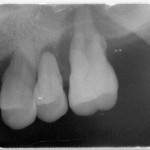

• 首屆「長庚植牙論壇」 聚焦All-on-X全口速定植牙引領精準植牙新時代 (17:09)

首屆「長庚植牙論壇」 聚焦All-on-X全口速定植牙引領精準植牙新時代

長庚醫院昨(11/30)日在林口長庚復健大樓會議廳舉辦體系首屆「長庚植牙論壇」,以「All-on-X全口速定植牙之過去、現在、未來」為主題,邀集國內外權威專家共同探討如何以更安全、快速且精準...

北榮桃園分院提醒牙周病隱形危機 別錯過治療時機

牙周炎是一種多因性、以牙菌斑生物膜為核心的慢性發炎疾病。維持牙周健康最直接且重要的關鍵之一,即是每日確實做好自我口腔清潔,當清潔牙齒不到位,牙周致病菌慢慢走向失衡狀態,便會引發持續性的牙周支...